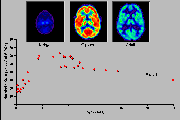

Click on one more more of the images above to view full-size image(s).

The images above are a simulation of relative glucose utilization. In infants 5 weeks of age and younger, glucose utilization is highest in the sensorimotor cortex, thalamus, brainstem and cerebellum. The rate of glucose utilization is relatively very low in the basal ganglia and cerebral cortex at this age. By about 3 months of age an increase in glucose utilization is seen throughout much of the cerebral cortex, and the rate in the basal ganglia approaches that of the thalamus. In addition, the sensorimotor cortex, already active at birth, continues to show increases in activity. The frontal cortex and several association cortical regions, however, remain less metabolically active than the rest of the brain. A pattern of glucose utilization resembling the adult is seen as early as 8 months and typically by 1 year of age. Taken together the data on patterns of cerebral glucose utilization support the thesis that there is a relationship between a metabolic increase within neuroanatomical structures and the emergence of corresponding function. For example, neonatal behavior is primarily dominated by subcortical brain structure activity. Intrinsic brainstem reflexes, such as the Moro, root and grasp reflexes, are prominent. Visuomotor function is present only in rudimentary form, and cortical function is mostly limited to primary sensory and motor areas. By 3 to 4 months, purposeless limb movements begin to be replaced by more coordinated motions as the infant reaches out for objects. The increasing metabolic rate seen in the cerebellar hemispheres and parietal cortex may be important in this context. By 8 to 9 months, the cognitive development is thought to begin in the human infant and the PET images now show increased glucose metabolism in frontal and association cortices, areas intimately involved with higher cortical function.

Click on image above to view full-size image.

The graph above represents average absolute glucose utilization (µmole/min/100g tissue) in the cerebral hemispheres of subjects of different ages. Note that although the pattern of glucose utilization at 1 year of age is similar to that of the adult, absolute values of glucose metabolism are lower in infants than in adults. Adult rates are evident by 2 years of age but the glucose metabolic rate continues to increase until approximately 9 years of age, when they begin to decline, reaching adult values in the latter part of the second decade of life. Phylogenetically old structures, such as the brainstem, that were mature at birth did not show this increase to excessive CMRGlc.

The high CMRGlc during 3 to 10 years corresponds to the period of exuberant connectivity in humans and is probably required to meet the energy demands of the neuronal processes and synapses that are also in excess by about a factor of two compared to adults. Shown above are PET scans from 3 different ages showing the relative glucose metabolic rate. Beneath the PET scans are drawings showing the relative complexity of the dendritic structure of cortical neurons. The progressive increase in glucose utilization seen in development is consistent with anatomical studies showing an expansion of dendritic fields (and synaptic connectivity) and an increase in capillary density in the human frontal cortex during the same period. Thus, it is possible that the decrease in glucose metabolic rate in the adult reflects a "pruning" of excessive neuronal connectivity and a selective stabilization of the remaining neuronal connections.